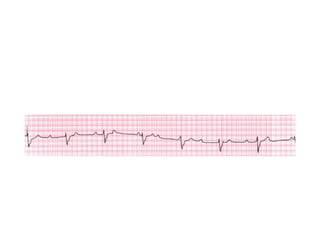

The document discusses several different cardiac conditions and test results including atrial fibrillation with complete heart block, second degree 2:1 heart block, complete heart block, atrial flutter with 2:1 block, amyloidosis indicated by an echocardiogram showing severe LVH, speckled appearance and low voltage limb leads on ECG, inferolateral reversible ischemia of moderate degree found on a graft study for a post-CABG patient which also showed an occluded superior OM and diseased OM2 and OM3 that were stented.